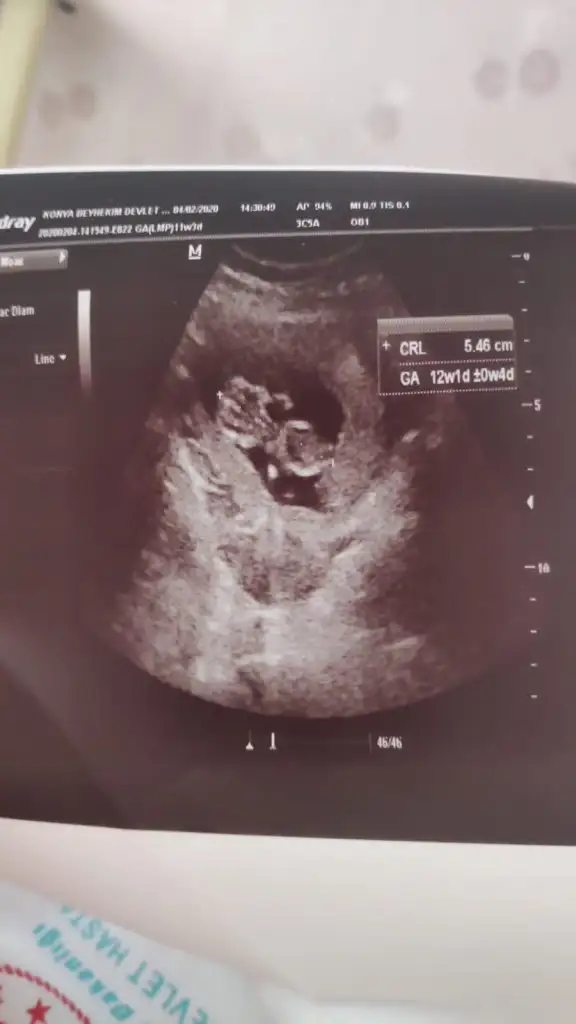

Erkek13+1 sizce ?

Kız gibi tam net degil başka ush paylaşın 12 de olır13+1 sizce ?

Başka usg varmı çok net değil diklik görünüyor sanki erkek gibi emin olamıyorum12 haftalık acaba cinsiyet tahmininde bulunabilir misiniz

Başka usg varmı çok net değil diklik görünüyor sanki erkek gibi emin olamıyorum

Yaa yukardan arkadaş bana mesaj yazıyorduYani şu gördüğüm nub ise dik görünüyor bacaklar yukarda nubunu değiştirmiyorsa pozisyon erkek gibiEki Görüntüle 2584968